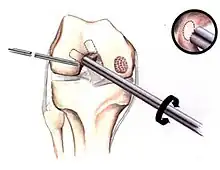

The articular cartilage along the border of the osteochondritis dissecans lesion -

Arthroscopic image of OATS surgery on the medial femoral condyle of the knee

Intact lesions

If non-surgical measures are unsuccessful, drilling may be considered to stimulate healing of the subchondral bone. Arthroscopic drilling may be performed by using an antegrade (from the front) approach from the joint space through the articular cartilage, or by using a retrograde (from behind) approach through the bone outside of the joint to avoid penetration of the articular cartilage. This has proven successful with positive results at one-year follow-up with antegrade drilling in nine out of eleven teenagers with the juvenile form of OCD,[53] and in 18 of 20 skeletally immature people (follow-up of five years) who had failed prior conservative programs.[54]